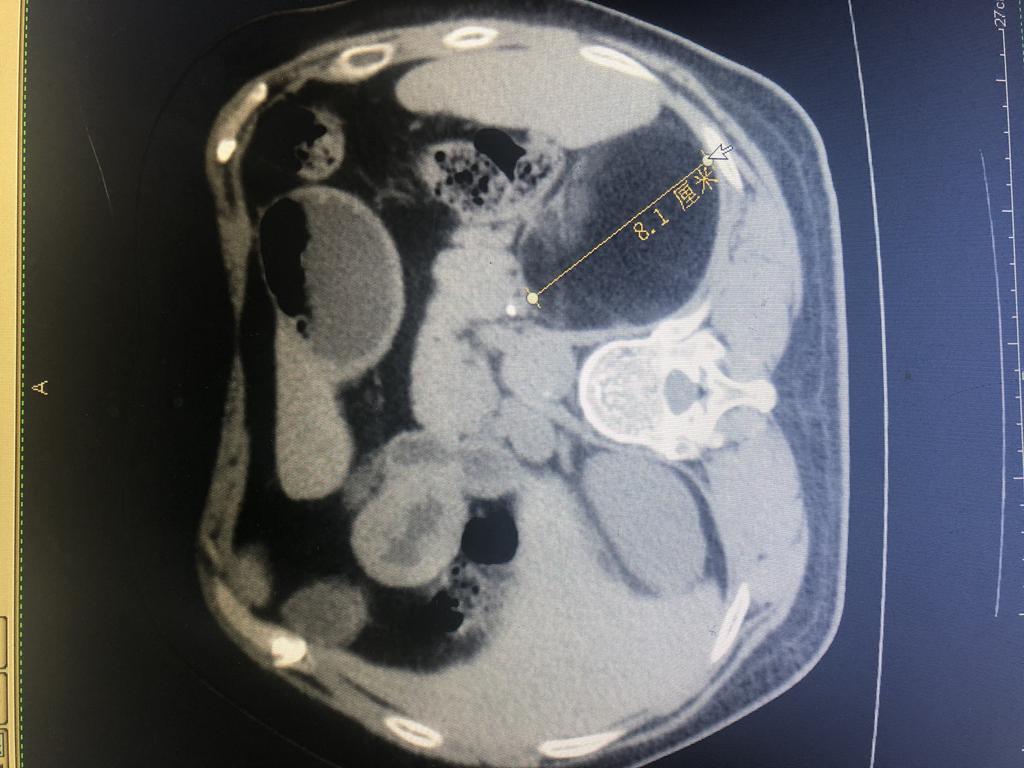

患者,女性,61岁,在乡镇医院体检发现左肾上腺有1个8×9cm巨大包块,遂来崇州市人民医院就诊后入泌尿外科住院治疗。因该患者左肾上腺包块大,泌尿外科主任杨华、副主任医师徐浩、医师彭思洋对患者的身体基础情况和病情进行反复评估,决定采取经腹入路行微创手术治疗。

肿瘤CT